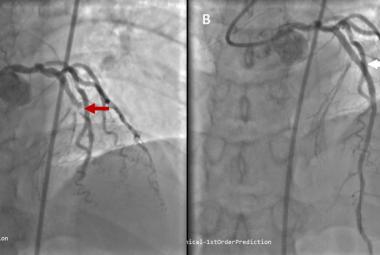

ERC traumatic cardiac arrest/ peri-arrest algorithm

Return of Spontaneous Circulation in Traumatic Cardiac Arrest Achieved by Traumatic-Based Resuscitation – A Case Report